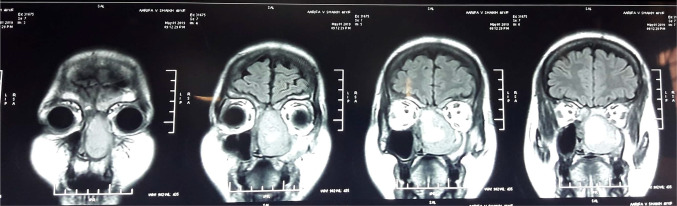

Before undergoing excision, MRI of brain was done for evaluating soft tissue extension. MRI showed focal abnormal signal density lesion in left nasal cavity with thick solid peripheral walls and septations. The lesion was hypointense on T2W and intermediate signal on T1W images and showed restricted diffusions on DWI & blooming on gradient images in septations and cystic component. It was causing deviation of nasal septum towards right side, laterally it was displacing medial wall of maxillary sinus and obstructing left osteomeatal complex. Superiorly it was extending into ethmoid sinus with retained secretions in bilateral frontal sinuses. There was no intraorbital and intracranial extension (Fig. 3).

Fig. 3.

Coronal MRI showing focal abnormal signal density lesion in left nasal cavity with thick solid peripheral walls and septations and was causing deviation of nasal septum towards right side, laterally it was displacing medial wall of maxillary sinus and obstructing left osteomeatal complex. superiorly it was extending into ethmoid sinus with retained secretions in bilateral frontal sinuses. there was no intraorbital and intracranial extension

A 41-year-old female was admitted in our Department in December 2016 for right chronic nasal obstruction and bleeding [epistaxis]. A contrast CT scan showed heterogeneously enhancing dumbbell shaped lesion measuring 4.8 cm × 4.6 cm × 1.7 cm [AP X CC X T] involving right maxillary antrum extending through ostium in right nasal cavity, right middle turbinate -meatus and abutting right inferior turbinate posteriorly and just protruding in post nasal space with changes of post-obstructive sinusitis in bilateral ethmoidal and right sphenoid sinus. No intraorbital and intracranial extension was seen. Biopsy was taken from the mass following which the nose had to be packed to control bleeding. Histopathological examination revealed Hemangiopericytoma. MRI of brain was done to reveal any oblivious soft tissue/ intracranial extensions. It showed a well defined expansile heterogeneously enhancing solid mass lesion in right nasal cavity with ethmoid sinuses involvement. There was focal destruction of posterior-superior nasal septum and extension of lesion into left posterior ethmoid sinus and nasopharynx. Right middle turbinate was not visualized separately from lesion and right inferior turbinate was compressed. There was no intraorbital and intracranial extension (Fig. 5).

Fig. 5.

MRI showing well defined expansile heterogeneously enhancing solid mass lesion in right nasal cavity with ethmoid sinuses involvement and focal destruction of postero-superior nasal septum and extension of lesion into left posterior ethmoid sinus and nasopharynx. right middle turbinate was not visualized separately from lesion and right inferior turbinate was compressed without intraorbital and intracranial extension